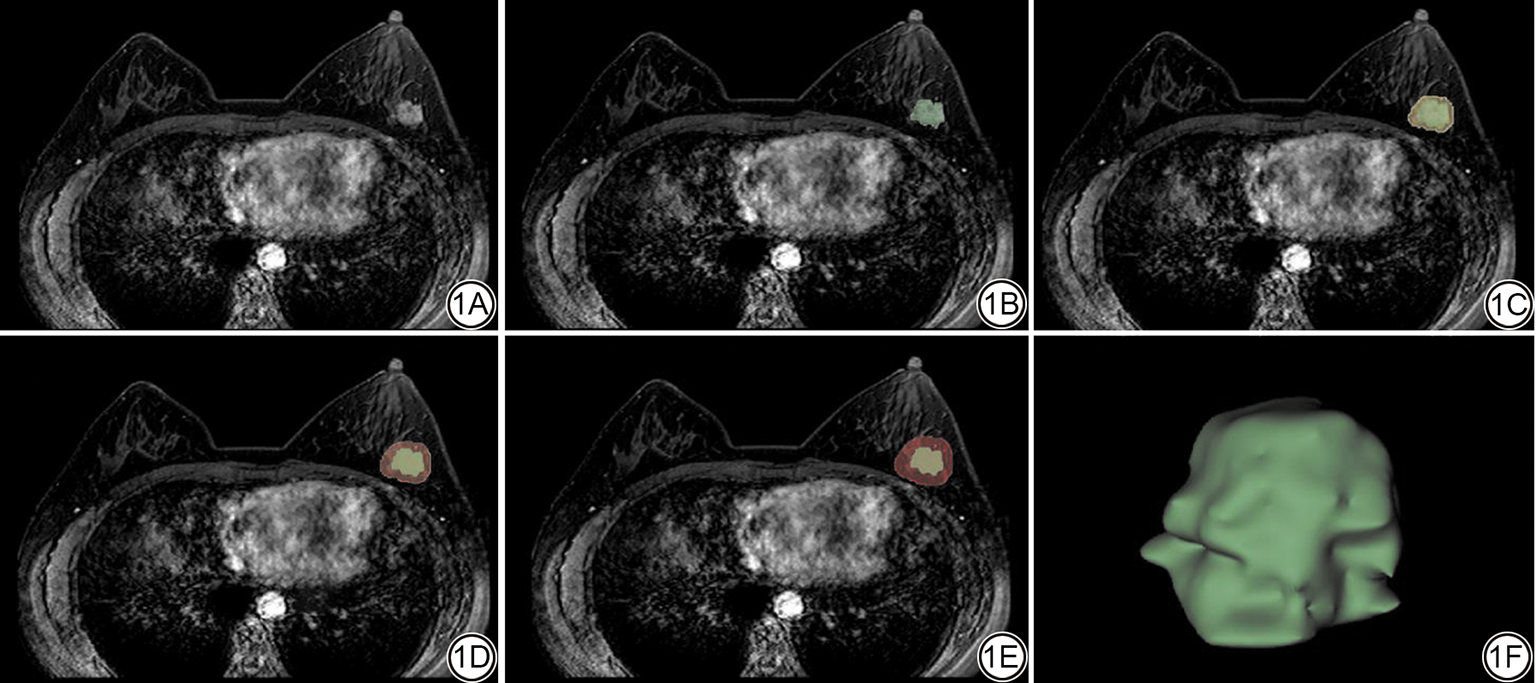

病灶的分割在ITK-SNAP 软件(版本3.8.0,www.itksnap.org)上完成。首先,对所有中心采集的图像进行预处理:(1)使用Ants软件将所有数据进行N4偏场校正以消除磁场不均匀对模型性能的影响;(2)以1 mm×1 mm×1 mm体素进行重采样,抹平各MRI设备间的空间分辨率差异;(3)采用Z-score归一化消除不同MRI扫描仪之间的灰度强度差异。随后,由2名具有5年以上工作经验的放射科主治医师在不知患者临床资料及对方标记结果的情况下,通过叠加每一层图像中的二维ROI,生成一个三维感兴趣区(volume of interest, VOI),2名医师统一勾画标准,勾画时避开明显的坏死、出血和囊变区。对30名随机选择的患者的VOI进行了手动独立分割,以评估观察者内部和观察者之间的可靠性。采用组内相关系数(intra-class correlation coefficients, ICCs)对同一观察者和不同观察者间的结果进行一致性评价,ICCs>0.75代表一致性良好。意见存在分歧时,通过共同讨论达成一致或由上级主任医师决定。对于多灶性病变,仅针对最大病灶进行图像分割和分析。大多数癌症的峰值增强多在注射对比剂完成的前2 min内[18],因此本研究选择DCE-MRI的第2期逐层进行勾画。瘤周ROI获取方法是以瘤内ROI的边界为基础根据形态自动外扩3、5、7 mm,如图1所示。如果瘤周区域的轮廓在扩张后延伸到乳腺实质之外,则手动去除实质以外的部分。

图1  ROI区域分割示意图。1A为乳腺原始图像;1B为瘤内ROI的手动勾画结果(绿色);1C、1D、1E分别展示以肿瘤边界为基准向外扩充3 mm(黄色)、5 mm(橘色)及7 mm(红色)后自动生成的瘤周ROI;1F为融合上述多层ROI后构建的三维肿瘤立体模型,直观呈现肿瘤及其周围不同环带的解剖关系。ROI:感兴趣区;DCE-MRI:动态对比增强MRI。

Fig. 1  Schematic illustration of ROI delineation. 1A: Original breast DCE-MRI. 1B: Manual outline of the intratumoral ROI (green). 1C to 1E: Automated peritumoral ROIs generated by expanding the tumor boundary outward by 3 mm (yellow), 5 mm (orange) and 7 mm (red), respectively. 1F: Three-dimensional reconstruction integrating all ROIs, offering a clear depiction of the tumor and its concentric peritumoral zones. ROI: region of interest; DCE-MRI: dynamic contrast-enhanced magnetic resonance imaging.